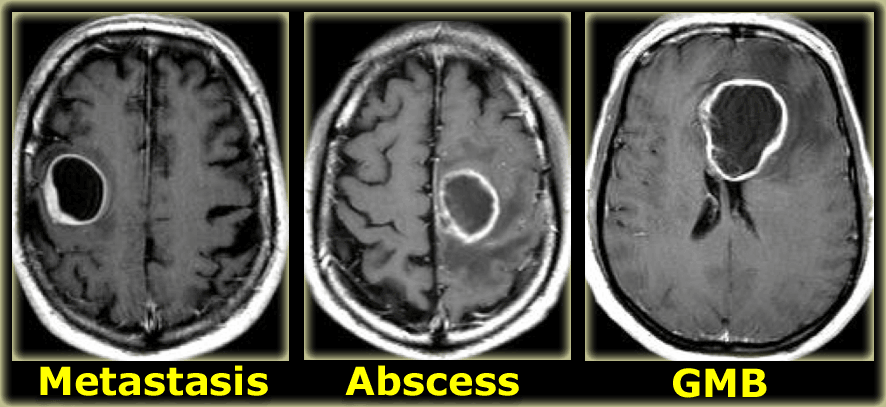

Ring enhancement

Ring enhancement is seen in metastases and high-grade gliomas.

It is also seen in non-tumorous lesions like abscesses, some MS-plaques and sometimes in an old hematomas.

On the left three different ring enhancing lesions.